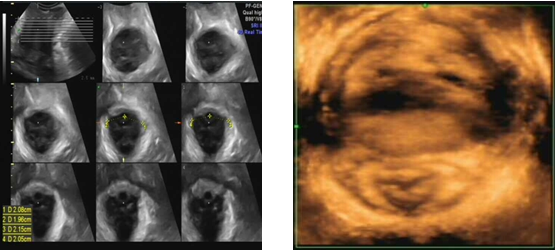

三维/四维盆底超声可以提示盆膈裂孔形态及大小变化,缩肛状态下评估双侧肛提肌有无损伤以及肛门括约肌的完整性,在Valsalva状态下测量盆膈裂孔面积,为盆腔脏器脱垂提供有用的信息,特别是肛提肌的损伤以及盆膈裂孔面积,有文献报道对于盆膈裂孔面积明显增大(>35cm2)且有肛提肌损伤的患者,其术后复发率增高。盆底超声对于产后患者的盆底损伤的预测有很大帮助,能够早期发现潜在压力性尿失禁、肛提肌的损伤以及肛门括约肌的损伤,并能及早告知加强锻炼预防盆底功能障碍性疾病的发生。最近有1例年轻患者,35岁,已顺产两胎,产后2年发现盆腔脏器脱垂,妇科检查时子宫脱出至阴道外,盆底超声检查,右侧肛提肌损伤,盆膈裂孔面积29平方厘米,提示单纯子宫脱垂,无阴道前后壁膨出。此患者如果产后能够超声及早发现盆底损伤,尽早锻炼可能会延缓发病年龄。

肛门括约肌完整(左图)

产后10年,肛门括约肌损伤(右图)

双侧提肛肌完整(左图)

双侧提肛肌损伤(右图)